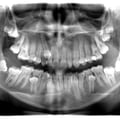

Імплантація 16,17,18 без врахування жодних правил оклюзії та знань в імплантології

Руйнування зубів - результат тривалого користування бюгельними знімними протезами

Лікування карієсу дистопованого 48 зуба не є вирішенням даної патології. Дистопія зуба мудрості провокує виникнення карієсу 47 зуба. Даний зуб має бути видалений

Пацієнтка А. (10 років). Первинна адентія внаслідок вродженої ектодермальної дисплазії

Відсутність адекватного лікування, як наслідок - 14,15 зуби приймають участь в акті дихання

Патологія прорізування зубів. Екструзія дистопії 23,24 ортодонтичним способом

Залізна людина )))

Неправильне зубне протезування - заклали зуби )))

Максимальна атрофія щелеп - результат тривалого користування знімними протезами

Міграція 28 зуба під очницю

Не кваліфіковане ендодонтичне лікування 36 зуба, як наслідок - вихід пломбувального матеріалу за межі кореня та проникнення його в нижньоальвеолярний канал та розвитком стійкої парастезії

Повна ретенція 44 зуба. Не раціональне зубне протезування

11,21,22,23 зуба приймають участь в акті дихання

Пацієнт Ж (17 років) - дистопія 35

Пацієнт Б (21 рік) - первинна адентія 13,23

Пацієнт Б (14 років) - множинна ретенція прорізування постійних зубів. Наявність закладки 9-тих зубів

Жертва, або студентів, або інтернів, або не кваліфікованих стоматологів. Результат - нераціональне зубне протезування при генералізованому пародонтиті, виведення пломбувального матеріалу за межі кореня в гайморову порожнину

фіксація металевого штифта за межі кореня. Ендодонто-ендоосальна імплантація, або п'яний ендодонт )))

Новоутворення кісткової тканини міжментальної ділянки

П'яний ендодонт, або "краще більше ніж меньше" - надлишок пломбувального матеріалу успішно інтегрувався в товщі слизової гайморового синуса

Реставрація 12,22 - альтернатива ортодонтії ))) Консоль 16,37 - альтернатива імплантації )))

Хронічний періодонтит 36 зуба - не успішне ендодонтичне лікування